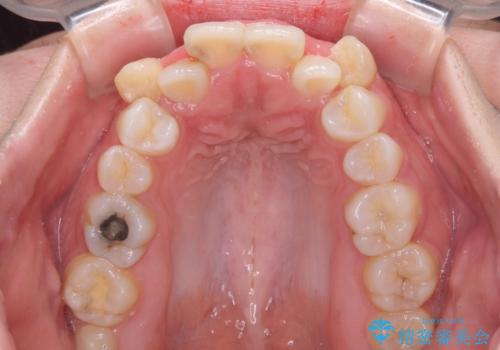

- 上下の八重歯やデコボコを気にして来院された患者様です。

上下ともに八重歯が顕著であったので、上下左右第一小臼歯4本を抜歯し、補助装置を使用して速やかに改善しながら、ワイヤー装置にて矯正治療を行うこととしました。

気になっていた八重歯は装置装着から3か月ほどで解消されました。

2年以内を目標として治療を開始しましたが、1年半ほどで終えることができました。